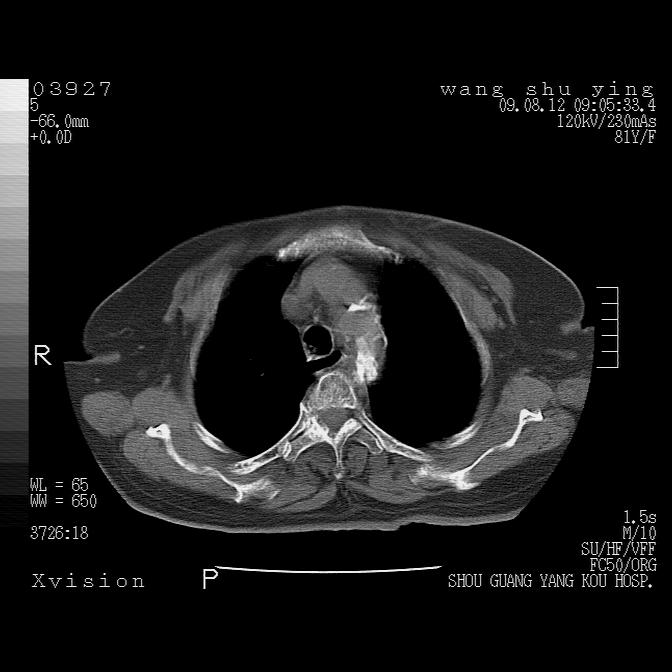

以下是引用帅河马在2009-8-12 12:59:00的发言:[br]两肺感染性病变伴双侧胸膜肥厚。[br]左侧甲状腺腺瘤不除外。[br]腹水+心包积液。[br][br][本贴已被 帅河马 于 2009-8-12 13:14:32 修改过]

以下是引用sdzyy在2009-8-12 18:17:00的发言:[br]两肺感染性病变伴双侧胸膜肥厚。[br]左侧甲状腺腺瘤不除外。[br]腹水+心包积液。[br]支持

以下是引用随光逐影在2009-8-12 19:42:00的发言:[br]1)两肺感染性病变伴双侧胸膜肥厚。2)不排除左侧甲状腺腺瘤。3)肝脏占位性病变;建议行进一步检查。